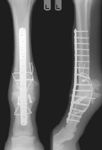

West LaFayette, Ind. - Tiny bone cracks caused by rigorous training usually are undetectable in horses before the cracks turn into hairline stress fractures or more serious problems, like the catastrophic bone failures that led to the deaths of at least three high-profile Thoroughbreds since 2006 and many others less well-known.